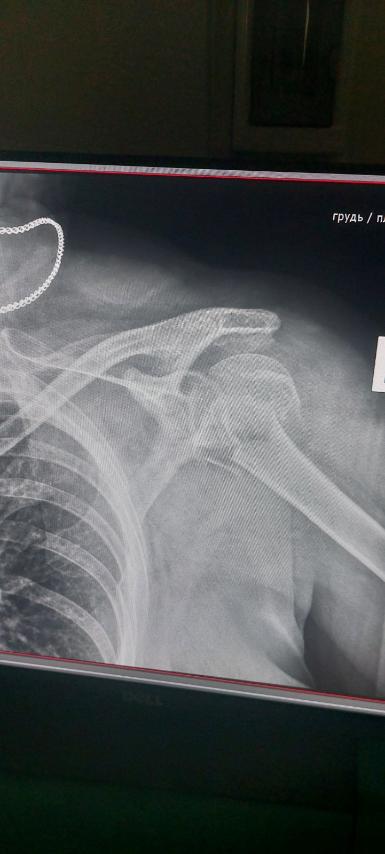

Добрый вечер всем. Прошу помощи на проведение операции сестре. Коротко. Сестре 60 лет. То руку ломала то ногу. Ну ломала и ломала всякое бывает. Недавно споткнулась упала и сломала два предплечья сразу. Врачи офигели если не написать хуже. Начали разбираться оказалось у нее Остеопороз. Хрупкие кости. Необходима сложная операция. Прошу помощи. Продаю Аську 300I 2016 г. + катуха NEL THUNDER 2020 г. Гарантия не закончилась. Аккумуляторы 8 шт. + зарядка, Фискарь. Завтра постараюсь разместить в соответствующем разделе. Цену уточню по сайту. На все есть документы. Все работает люкс. Карта ПБ 4731 2191 2583 1887 Коровкин Олег Анатольевич. Будем благодарны я и сестра. Заранее спасибо.

лена (2).jpg

лена.jpg